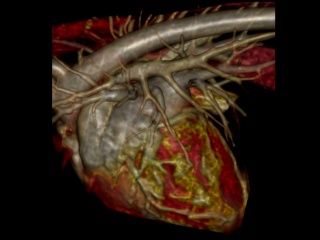

Nous avons fait le choix d’un scanner 80 barrettes

Un scanner 80 barrettes offre une acquisition très rapide avec des coupes fines et des reconstructions 2D/3D précises.

- Injection systématique de produit de contraste avec un injecteur automatique synchronisé pour des temps artériels, portaux et veineux de qualité et une lecture plus fiable.

- Thorax & voies aériennes : recherche de masses, corps étrangers, dilatations, bronchopathies ; étude des vaisseaux (angiographie).